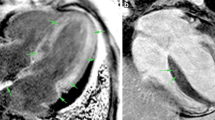

Survival of patients was stratified by the risk classification according to the Rad-score cut-off value of 0.66, which was the best predictor of survival (HR 8.91; 95% CI, 3.89–20.44; p < 0.001) (Fig. 4). The survival curve indicates that there is an approximately 84% chance of survival at 12 months in patients with the Rad-score < 0.66 compared with 33% for patients with Rad-score ≥ 0.66. Figure 5 shows the radiomics analysis and prognosis correlation from LGE images of three CA patients, which suggests that radiomics model is a better prognostic assessment for CA.

Representative LGE images of CA patients. Panel A Base, mid, and apex—LV short-axis LGE MR images depict a focal, patchy LGE pattern in a 62-year-old woman with CA. This patient had no adverse events during 3 years follow-up. Panel B A 36-year-old male patient had transmural LGE at the base and subendocardial LGE in the middle and apical sections of LV. This patient died suddenly after 1 year of follow-up. Panel C A 59-year-old man had a low LGE extent but a high Rad-score of 0.83 (> 0.66), who died of cardiac arrest during 1 year of follow-up